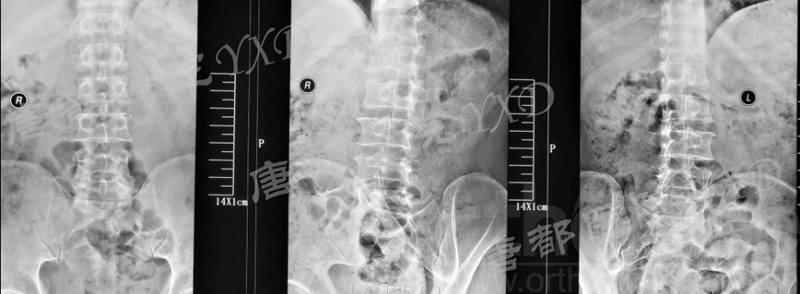

影像学检查:

诊断:腰椎椎间融合术后融合器后移

手术方案:显微镜辅助MI-TLIF腰椎翻修术